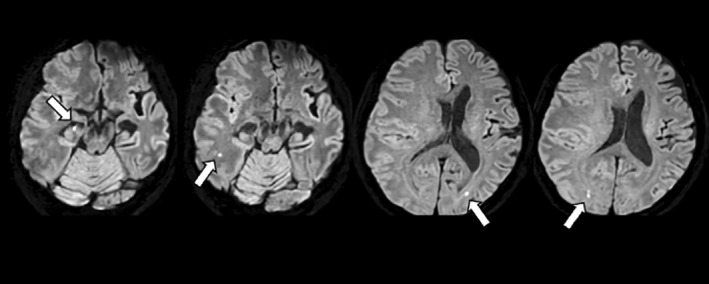

A case of severe ARIA with multiple infarctions and extensive microbleeds following lecanemab administration.